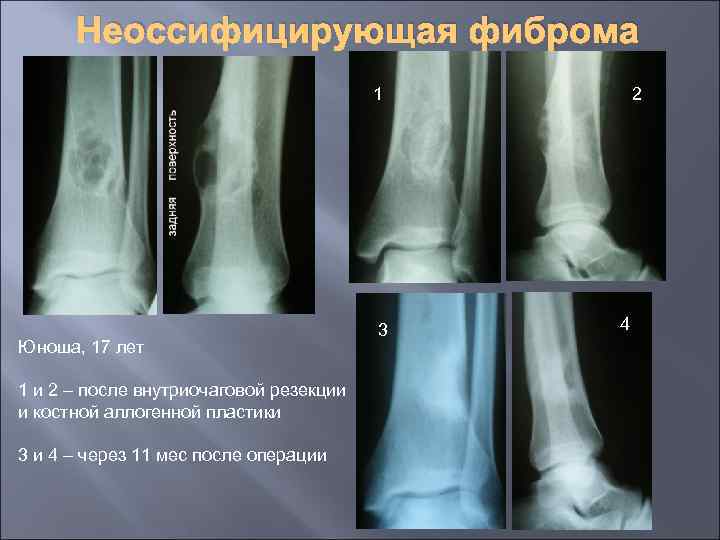

Неоссифицирующая фиброма 1 Юноша, 17 лет 1 и 2 – после внутриочаговой резекции и костной аллогенной пластики 3 и 4 – через 11 мес после операции 3 2 4